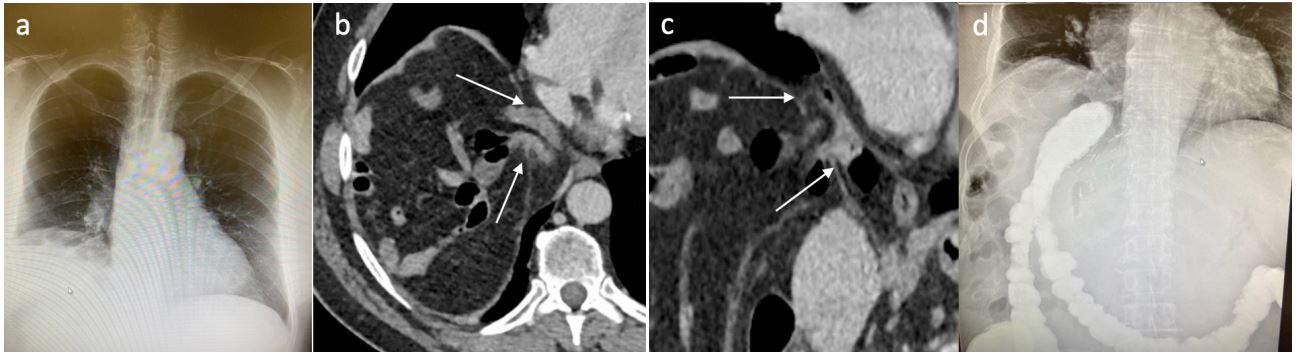

In the context of intermittent epigastric pain, the patient was readmitted to the emergency department 42 months post-hepatectomy. The blood test results were normal. Right basal condensation and costophrenic angle blunting were observed on the chest radiography (Figure 2A). Thoracoabdominal computed tomography (CT) showed elevation of the right hemidiaphragm with DH of the colon, but no sign of bowel obstruction or colic ischemia (Figures 2B, 2C). Contrast radiography of the colon did not confirm herniation DH of the colon, only showing the elevation of the right half of the diaphragm with the colon that was located just below (Figure 2D). Therefore, except for the first CT scan, no other examination could highlight DH. For completeness, the patient also underwent gastroscopy and colonoscopy, both of which were normal.

Figure 2: Diagnostic work-up of DH: a. chest X-ray: right diaphragm’s elevation; b-c: axial and coronal CT (arrows: defect’s limits); d: colon X-ray.